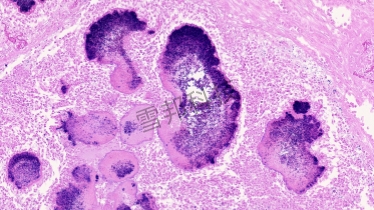

革兰氏染色是用来鉴别细菌的一种方法,细菌细胞壁上的主要成份不同,利用这种染色法,可将细菌分成两大类,即革兰氏阳性菌与革兰氏阴性菌。革兰氏染色的对象是细菌的细胞壁,染色后细菌与环境形成鲜明对比,可以清楚地观察到细菌的形态、排列及某些结构特征,而用以分类鉴定。